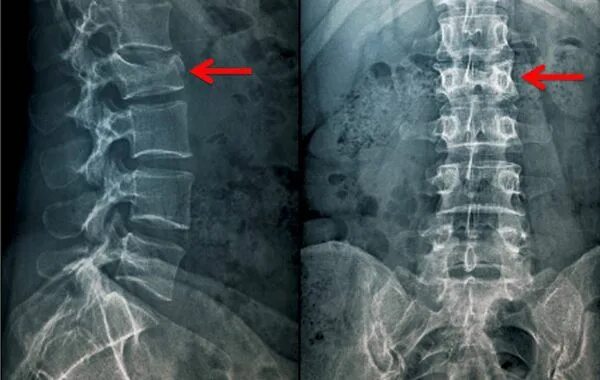

Перелом позвонка инвалидность